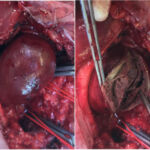

Ανεύρυσμα κοιλιακής αορτής-Ανοιχτή Αποκατάσταση

Η ανοιχτή αποκατάσταση ανευρύσματος κοιλιακής αορτής είναι χειρουργική επέμβαση κατά την οποία το παθολογικά διατεταμένο τμήμα της αορτής αντικαθίσταται με συνθετικό αγγειακό μόσχευμα για την αποκατάσταση της φυσιολογικής ροής του αίματος.